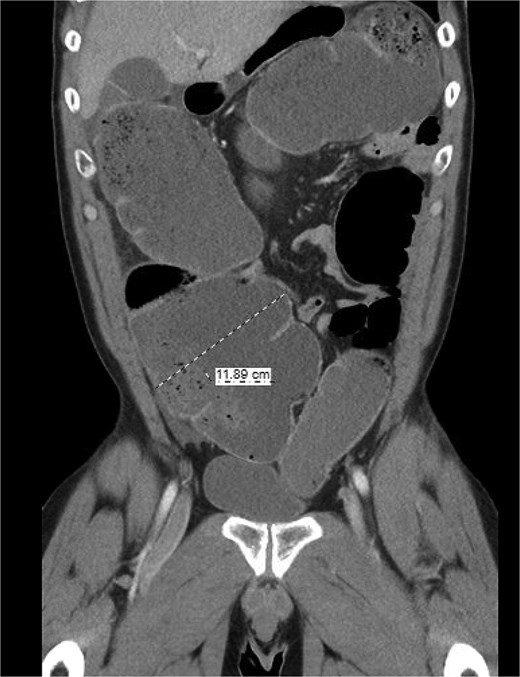

The patient was a 49-year-old male with a past medical history of anxiety and constipation who originally presented to the emergency department complaining of 1 day of worsening generalized abdominal pain, obstipation, nausea, and chills. Of note, he had undergone a colonoscopy 3 months prior to presentation, where two benign polyps were removed. There were no signs of inflammatory bowel disease. Upon examination, he was noted to be tachycardic to 130, with a blood pressure of 90/70 after 2 L of intravenous fluid resuscitation. His abdomen was distended and diffusely tender with peritoneal signs. Laboratory analysis showed a white blood cell count of 26 000, creatinine of 1.8, and a lactic acid of 7.9. A CT of the abdomen/pelvis revealed a cecum of 12 cm filled with liquid stool, but no pneumoperitoneum, pneumatosis, or colonic wall thickening. Figures 1 and 2 demonstrate the axial and coronal images of the dilated colon, respectively.

Coronal imaging demonstrating significant colonic dilation up to 11.9 cm in the cecum.